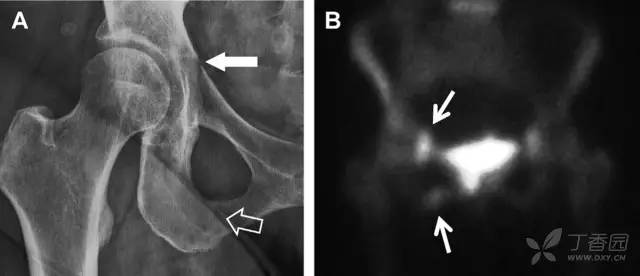

耻骨骨折

具有持续损伤因素的耻骨支骨折,可能看似轻微,尤其是合并骨质疏松的患者。因此,特别需要注意皮质缺损和骨密度改变。长跑运动员易发生耻骨应力性骨折,常常发生在靠近耻骨联合的下支。由于这些骨折为非移位骨折,所以常常被忽视。

图 3 自行车事故患者,侧方受力的髋臼前柱/耻骨骨折。A 正位平片示右侧髂耻线轻微中断(实箭头),此处异常最初并未发现。此外,右下方其实还有一处轻微耻骨支骨折(空箭头)。B 10 天后行骨闪烁显像证实了髋臼前柱骨折和侧耻骨下支骨折(箭头)。值得注意的是,左侧前柱亦存在异常